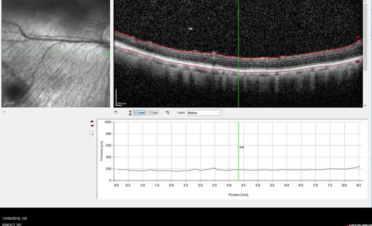

OCT del segmento posterior

Haremos una OCT del segmento posterior cuando necesitemos:

- Medir las diferentes capas de fibras de la retina y el nervio óptico. Con este tipo de OCT realizamos un corte histológico en vivo de las diferentes capas del fondo ocular: retina, nervio óptico y coroides pudiendo llegar incluso hasta la esclerótica.

- Valorar cambios en la estructura, como por la presencia de exudados, hemorragias, degeneraciones,

edema, membranas epirretinianas, anomalías del vítreo posterior ….